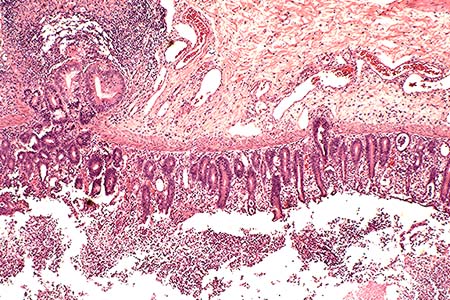

Case 3-1. Colon. Demonstrates erosive colitis with lymphoid depletion, herniation of crypt glands into the submucosa, and intraluminal fibrinosuppurative exudate. 20x

AFIP Diagnosis: Colon: Colitis, erosive, suppurative, subacute, diffuse, severe, with lymphoid depletion, abundant intraluminal suppurative exudate and numerous bacilli, Rhesus monkey (Macaca mulatta), primate.

The colon contains large, focally extensive to confluent areas of mucosal ulceration which are covered by a layer of fibrinopurulent material with hemorrhage. The remaining lamina propria is increased in cellularity due to mononuclear cells with occasional neutrophils. Crypts are dilated and filled with degenerative inflammatory and epithelial cells. Re-epithelialization is occurring along the luminal surface of the mucosa in some areas. The submucosa is markedly edematous with dilated lymphatics, and scattered inflammatory cells. The tunica serosa is also edematous and mildly to moderately infiltrated with mononuclear cells. There are focal hemorrhages on the serosal surface and mesothelial cells are hypertrophic.